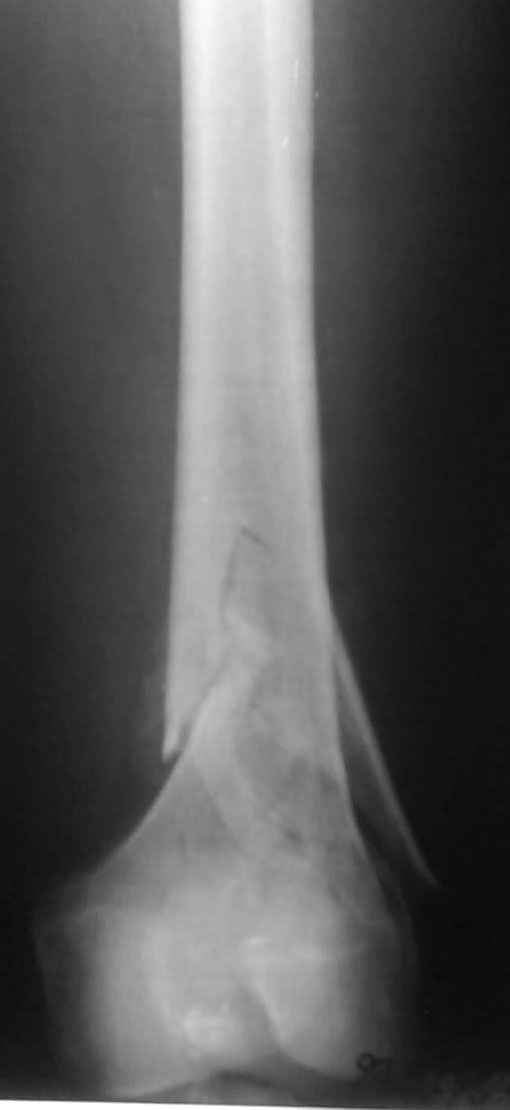

К нам поступил пациент 25 лет с закрытыми переломами обех бедренных

костей, прошел месяц после травмы. Слева-внутрисуставной перелом,

поэтому  выбор здесь очевиден, открытая репозиция, стабильная

фиксация, скорее всего LCP DF, а справа - мнения учёных, как

говорится, разошлись. Лично я, как лечащий врач, за закрытый

интрамедуллярный остеосинтез DFN. Со мной согласна половина

коллектива, другая - за интрамедуллярный остеосинтез (DFN,UFN) но с

открытой реопозицией, поскольку при закрытой методике все осколки

останутся где-то сбоку, получится дефект и вдруг не срастется!